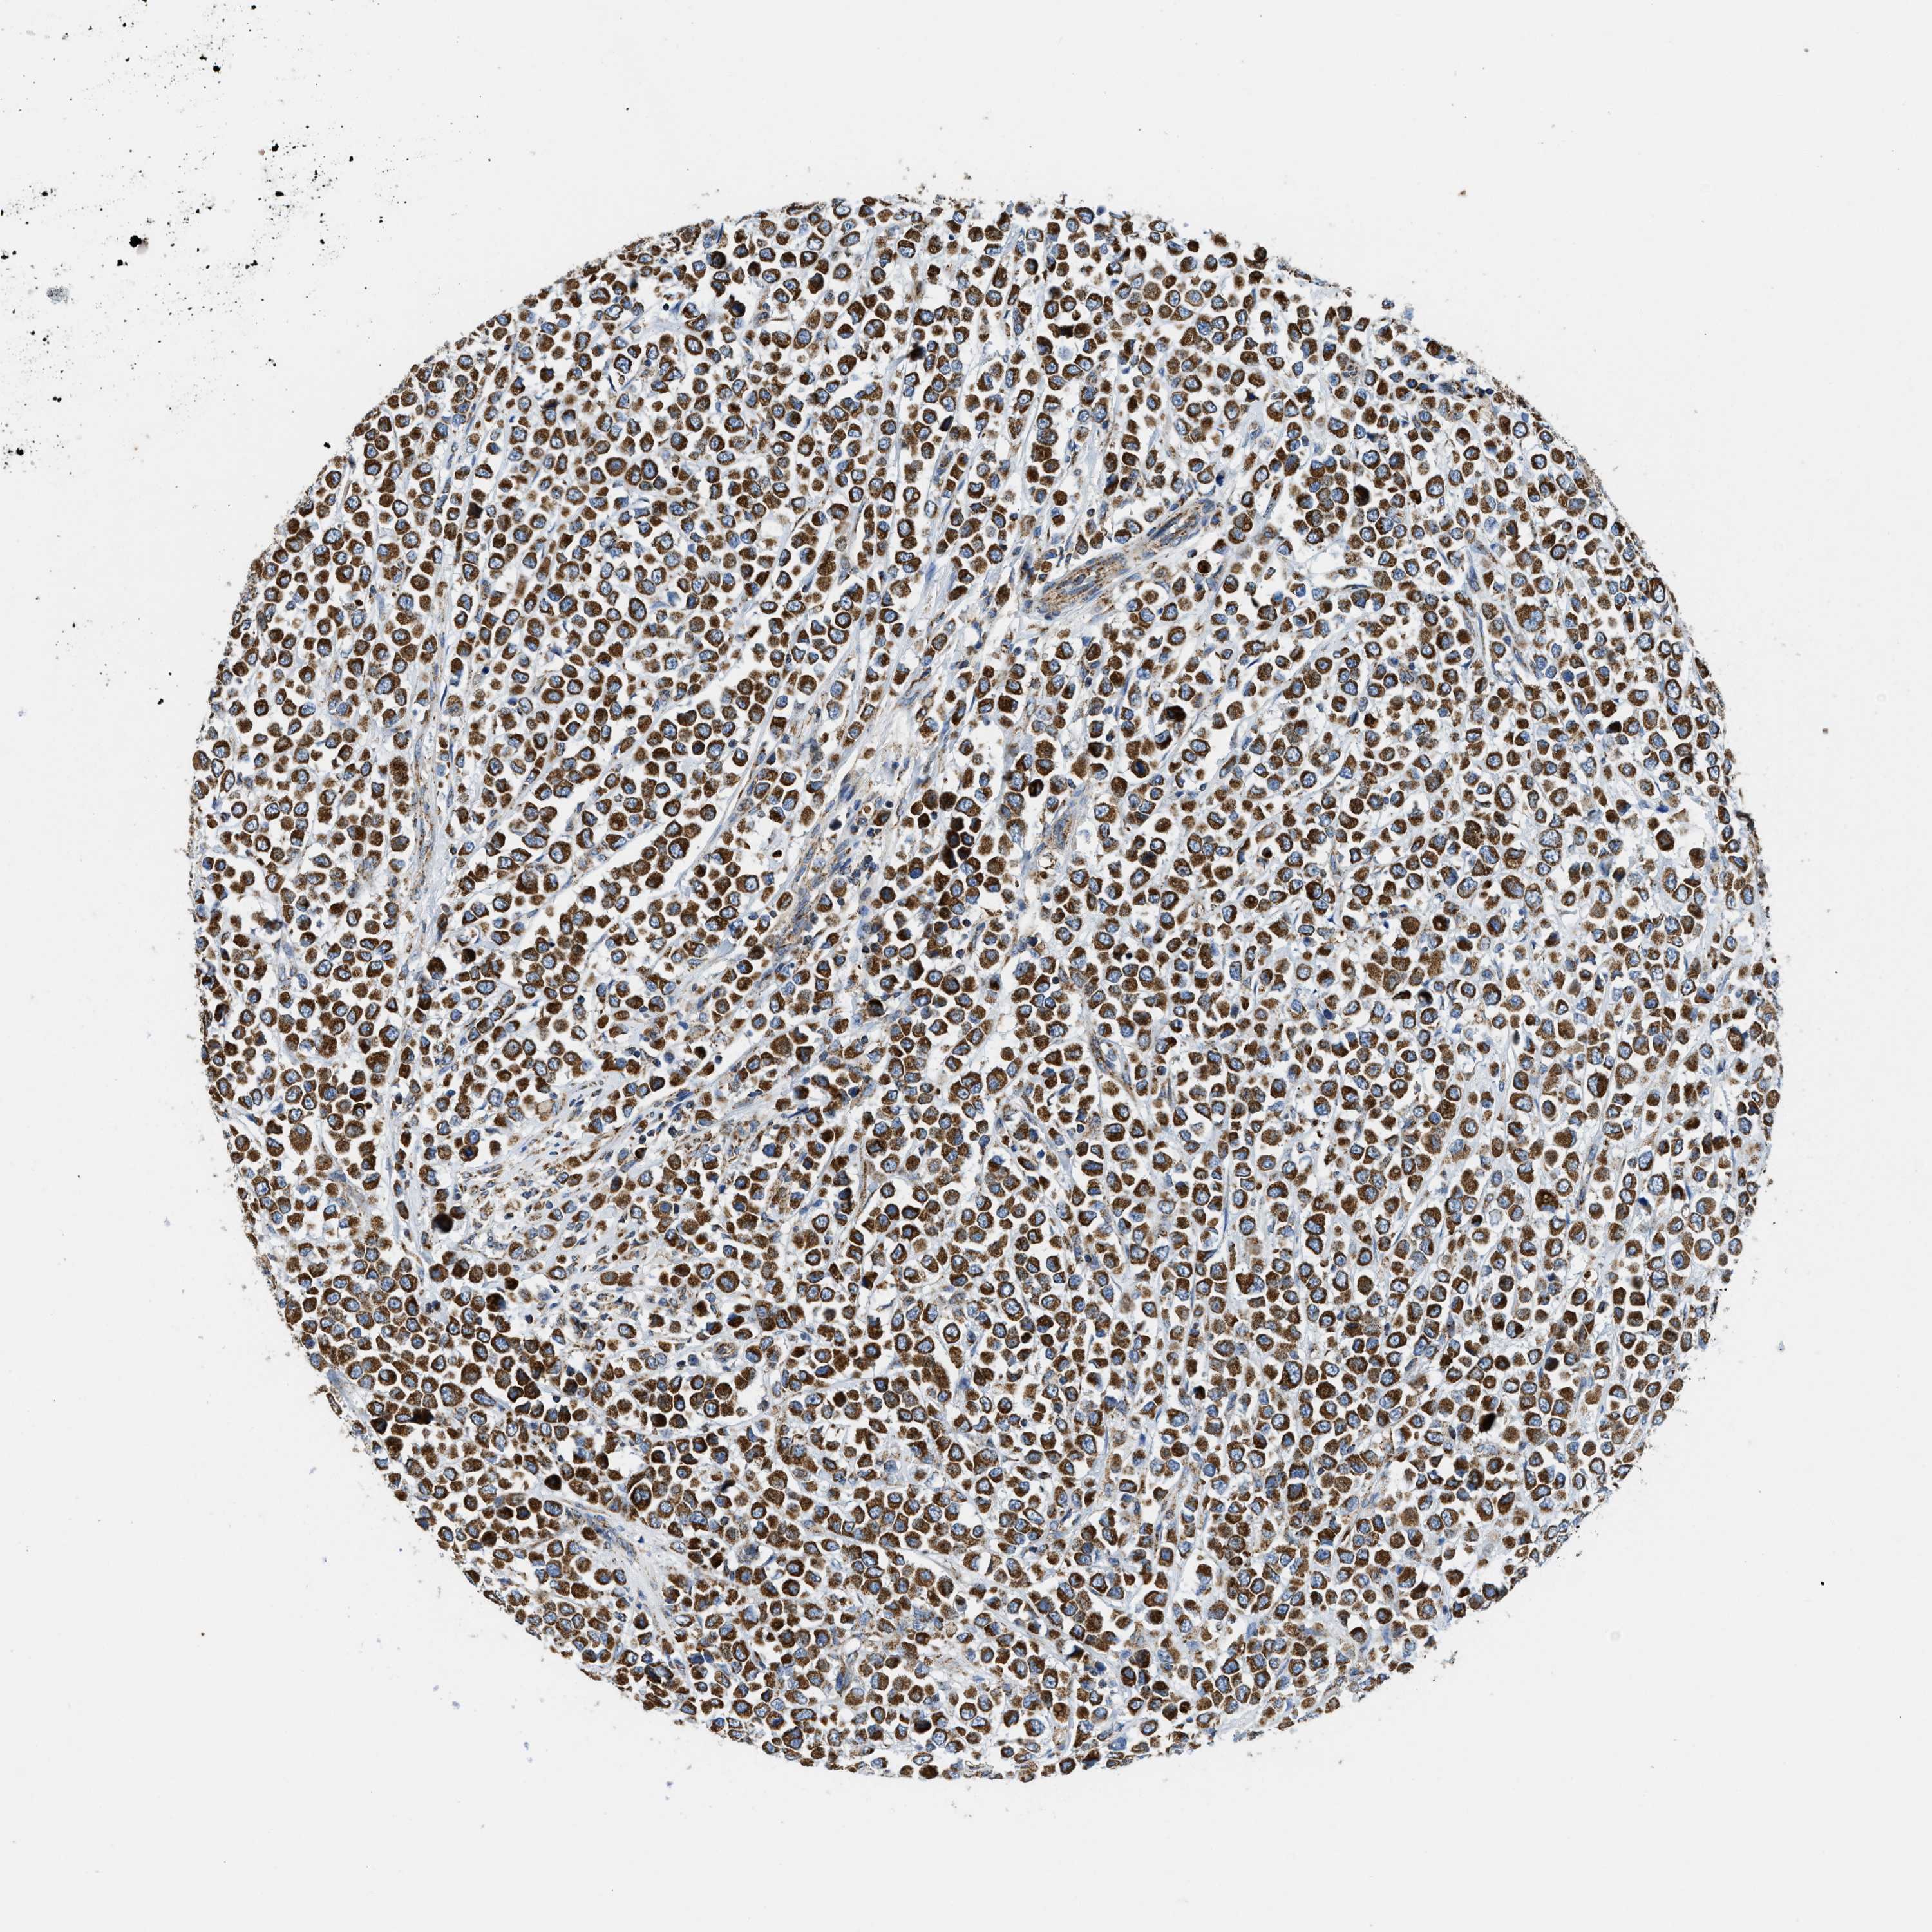

CANCER BREAST CANCER Show tissue menu

BRCA TCGA BRCA VALIDATION PROTEIN EXPRESSION